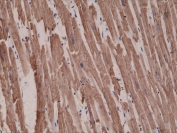

IHC testing of FFPE human heart tissue with recombinant ACTC1 antibody at 1:1000.

In immunohistochemistry, the Recombinant ACTC1 antibody highlights sarcomeric actin filaments in cardiac muscle tissue, producing a striated staining pattern characteristic of organized sarcomeres. In immunofluorescence, it visualizes cytoskeletal architecture in cardiomyocytes, allowing detailed study of contractile assembly and remodeling. In western blotting, the antibody detects ACTC1 protein in heart tissue extracts, providing a quantitative measure of expression levels. Recombinant production ensures consistent specificity and eliminates variability often associated with polyclonal antibodies.